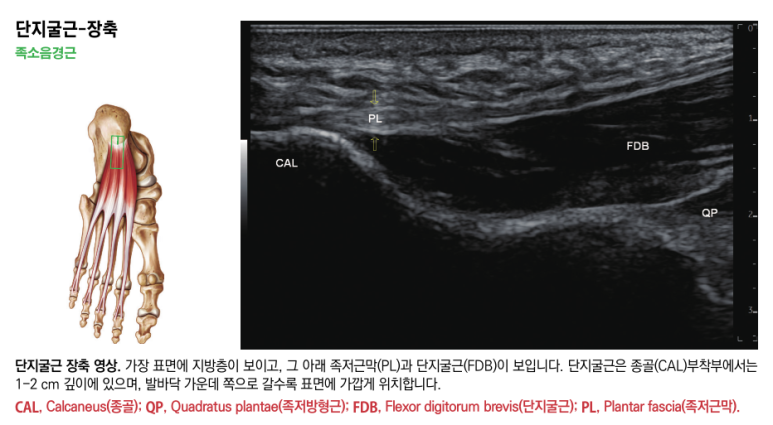

위 사진은

제가 집필한 근육초음파 서적의

족소음경근 영상입니다.

그림에서 화살표 표시한

부위가 족저근막인데요.

꼼꼼하게 촉진해서

눌렀을 때 민감한 통증이 느껴지는

혈자리를 손끝 감각으로 찾아내고요.

이어서 경혈 초음파로재확인합니다.